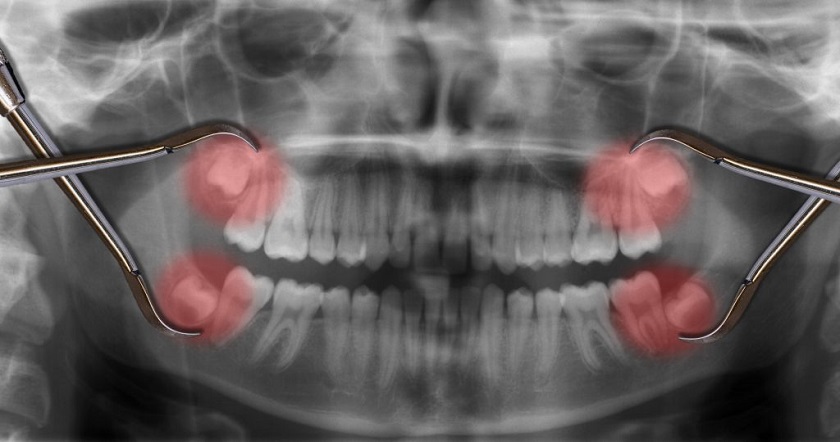

Những chiếc răng khôn thường mọc ngược, mọc ngầm, mọc nghiêng, mọc kẹt do không có không gian để “cư ngụ” trên cung hàm. Chúng có thể mọc ngược về phía xương hàm, đâm thẳng về phía răng hàm lớn thứ hai hoặc có thể mọc bình thường, nhú được lên khỏi nướu được một phần thì tắc và ngừng mọc vĩnh viễn gây ra nhiều vấn đề khác nhau cho sức khoẻ răng miệng.

Thực tế, mỗi người có đến 32 chiếc răng vì thêm 4 răng khôn, 2 cái ở hàm trên và 2 cái ở hàm dưới, chúng sẽ mọc cuối cùng, sau 28 chiếc răng. Vấn đề xảy ra khi răng khôn mọc là không còn đủ chỗ trên xương hàm để có thể mọc thẳng bình thường, nên thường sẽ mọc theo hướng khác.

Răng khôn có thể mọc ngược về phía xương hàm, đâm thẳng về phía răng số 7 bên cạnh hoặc có thể mọc bình thường, nhú lên khỏi nướu được một phần thì bị tắc và ngừng mọc vĩnh viễn.

Mỗi người có đến 4 chiếc răng khôn